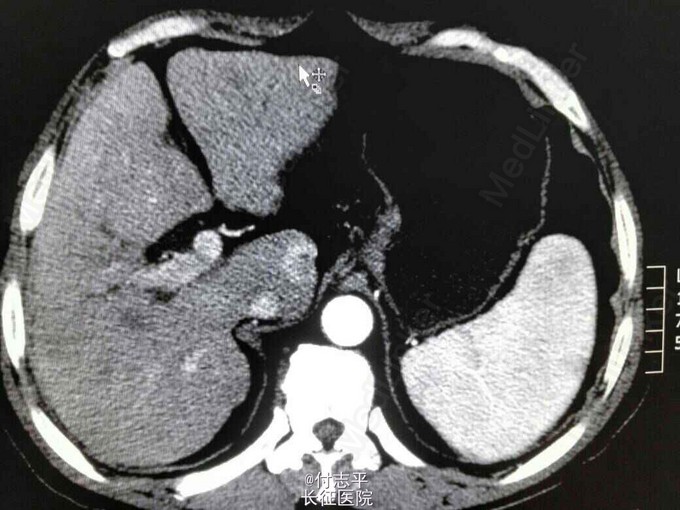

主诉:体检发现AFP升高2月,发现肝占位6天。 病史:患者63岁男性,2个半月前在当地体检发现AFP260.6ng/ml,门诊B超示肝硬化,因无任何伴随症状,未进一步检查。10天前复查 AFP570.3ng/ml,仍未行处理。遂来我院,门诊增强CT示肝尾装叶占位,肝硬化,脾大,脂肪肝,胆囊切除术后。患者一般情况尚可。3年前体检发现“乙肝病毒感染,肝硬化”,抗乙肝病毒治疗“恩替卡韦”至今。40年前因胆结石行胆囊切除术。长期饮酒史,服药后开始戒酒。无家族病史。

诊断:1.原发性肝癌。2.乙肝后肝硬化。3.胆囊切除术后。 治疗:完善术前检查后预备行肝尾状叶占位微波消融术。术中见小肠、大网膜、与原切口瘢痕和肝脏脏面广泛粘连,仔细分离暴露后见肝脏呈轻中度结节性肝硬化表现,质地较硬;于尾状叶实质内探及2cm质硬肿块,边界不清,周围组织及器官未见明显侵犯。由于肿瘤位置较深,超声探头不好摆放,改行肝尾状叶切除术。